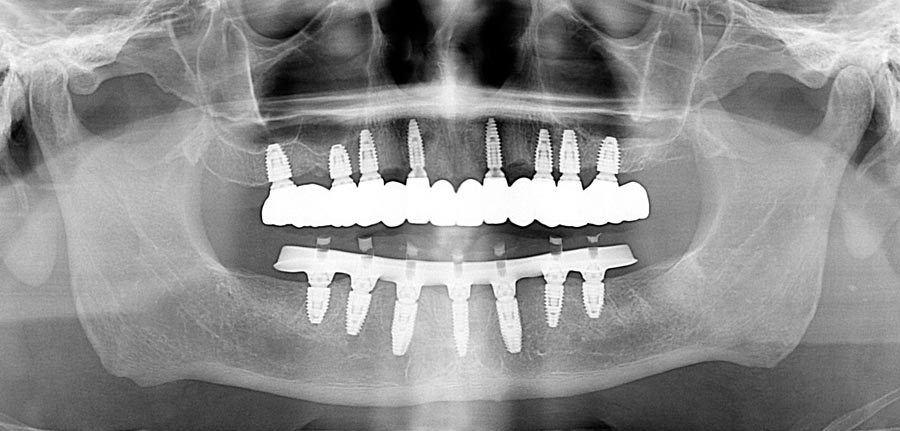

Post-treatment panoramic image. This treatment is as good as humans can do in 2025. This patient was undecided whether to keep his teeth. We gave him the chance to consider this option but later he decided to have full mouth implants. We changed gears and were able to deliver World Class outcomes. We continue to encourage better homecare. This patient is from out of state so we haven’t seen his tissues in almost a year.